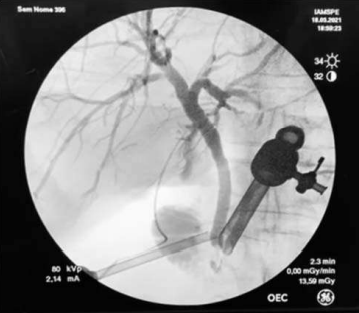

A principal indicação do exame acima seria